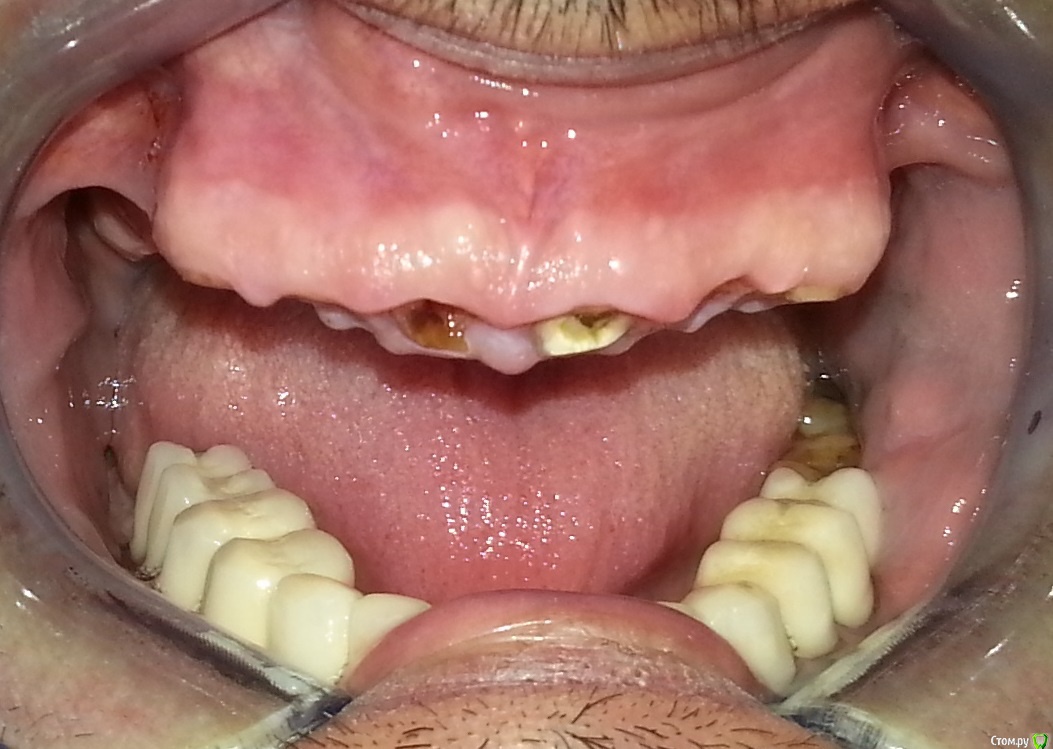

Nitrino1 Опубликовано 6 февраля, 2017 Поделиться Опубликовано 6 февраля, 2017 (изменено) Здравия желаю коллеги) Нужен совет опытных коллег, так как сам еще мало имею опыта в таких работах) Из анамнеза, был фронт мк, сначала расцементировка с одной стороны, и далее сломались зубы как видно на фотках. Хочет сохранить фронт своими зубами. Я посмотрел, как мне показалось реально вырулить если создать феррул в 2 мм. А после клыков уже имплантами восстаналивать. На данный момент перелечиваю 13й, попытался создать феррул в 2мм, на фотке можете увидеть. Как вы считаете, иду к успеху или к провалу? Что посоветуете?Вопросы:1. Беспокоит ситуация с 23им зубом, точнее с его апроксималкой (смотри ОПТГ), как поступить? Есть шанс сохранить зуб?2. Если получится сделать мост с 13-го зуба по 23-й зуб, тогда как поступить? Сделать вкладки , далее мк. А потом уже переходить к имплантам? Просто до завершения лечения на имплантах, пройдет 4-5 месяцев, за это время он не выбьет фронт нижними зубами? В Розинштиле написано что при восстановлении всей челюсти, лучше начать с фронта, создать эстетику на планируемую высоту а далее уже задние зубы под эту высоту...Буду рад любым дельным советам и рекомендациям)П.С. удалить сразу, самый простой способ)) П.П.С Последняя фотка, это после удлинения 13зуба) тоже буду рад замечаниям Изменено 6 февраля, 2017 пользователем Nitrino1 Ссылка на комментарий